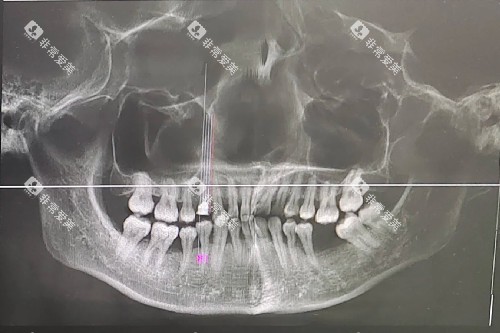

该口腔机构引进了一系列靠前的口腔治疗设备,如口腔CT、智能化牙片机等。

这些设备能够更更准地诊断牙齿问题,为治疗提供有力的支持。